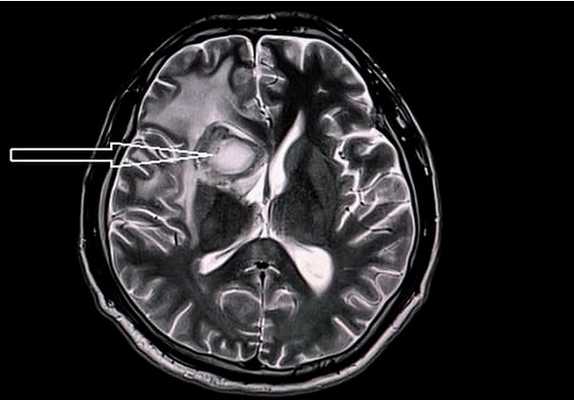

Абсцесс головного мозга на МРТ (указан стрелкой)

Гиперинтенсивные очаги

Выявление гиперинтенсивных, т.е. ярко выделяющихся на МР-сканах, очагов заставляет специалиста подозревать опухоль головного мозга, в том числе метастатического происхождения, гематому (в определенный момент от начала кровоизлияния), ишемию, отек, патологии сосудов (каверномы, артерио-венозные мальформации и пр.), абсцессы, обменные нарушения и т.п.

Лакунарный инфаркт головного мозга на МРТ (указан стрелкой)

Заподозрить нарушения церебрального кровообращения можно по очаговым изменениям периваскулярных пространств Вирхова-Робина. Последние представляет собой небольшие полости вокруг мозговых сосудов, заполненные жидкостью, через которые осуществляется трофика тканей и иммунорегулирующие процессы (гематоэнцефалический барьер). Появление гиперинтенсивного МР-сигнала указывает на расширение периваскулярных пространств, поскольку в норме они не видны.

Очаги ишемии на МРТ

Очаги ишемии

Нарушения мозгового кровообращения приводят к кислородному голоданию тканей, что может спровоцировать их некроз (инфаркт). Ишемические очаги при Т2 взвешенных последовательностях выглядят как зоны с умеренно гиперинтенсивным сигналом неправильной формы. На более поздних сроках при проведении в Т2 ВИ или FLAIR режиме МРТ единичный очаг приобретает вид светлого пятна, что указывает на усугубление деструктивных процессов.